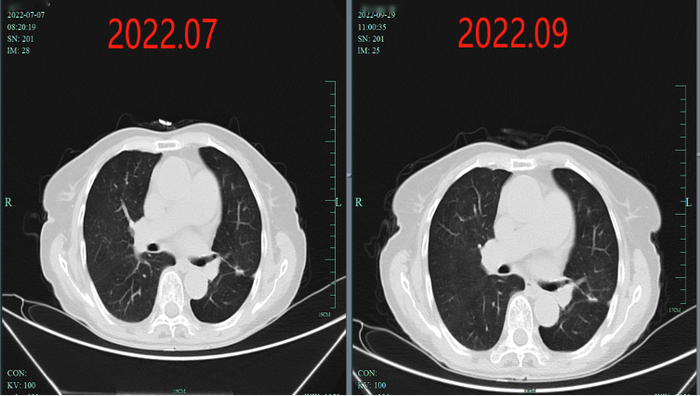

疗效评估:复查时原发灶较基线时明显缩小,达到深度缓解,并在随后治疗中持续缓解长达39个月。

上述病例为初诊转移性NSCLC患者,在基因检测明确BRAF V600E突变后,接受达拉非尼+曲美替尼一线治疗。在服药1月余后复查肺部CT,原发灶较基线时明显缩小,疗效评价达到深度缓解。截至2023年11月最后一次随访,该患者已获得长达39个月的PFS。该病例的治疗过程再次印证了达拉非尼+曲美替尼一线治疗的长生存获益。